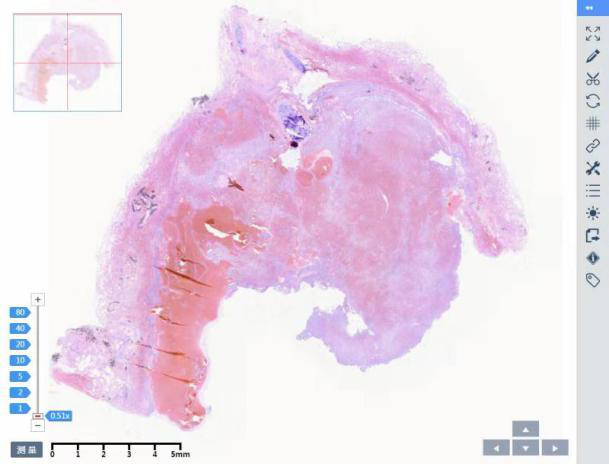

病理切片:

病例二:由北京协和医院提供